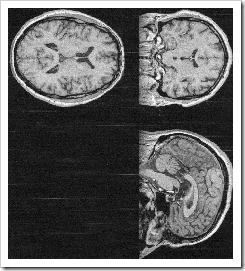

PC_Has_A_Brain_Shock_0001 PC_Has_A_Brain_Shock_0002I've heard suggestions that I haven't got a brain, and if I did I've never used it.  I know, I've heard you.  But me baby, I've got statistics, I've got facts.  I've got pictures.

Herewith the shocking evidence: actual picture proof that I both have a brain and, from those few splodges of colour there, that I sometimes even use it.  Frightening, isn't it.

(The pics, by the way, come from a scan done as part of a stroke study, for which the researchers needed some normal brains.  I did warn them about the inherent risk in using mine, but you just can't tell some people anything.  I've learned that.)